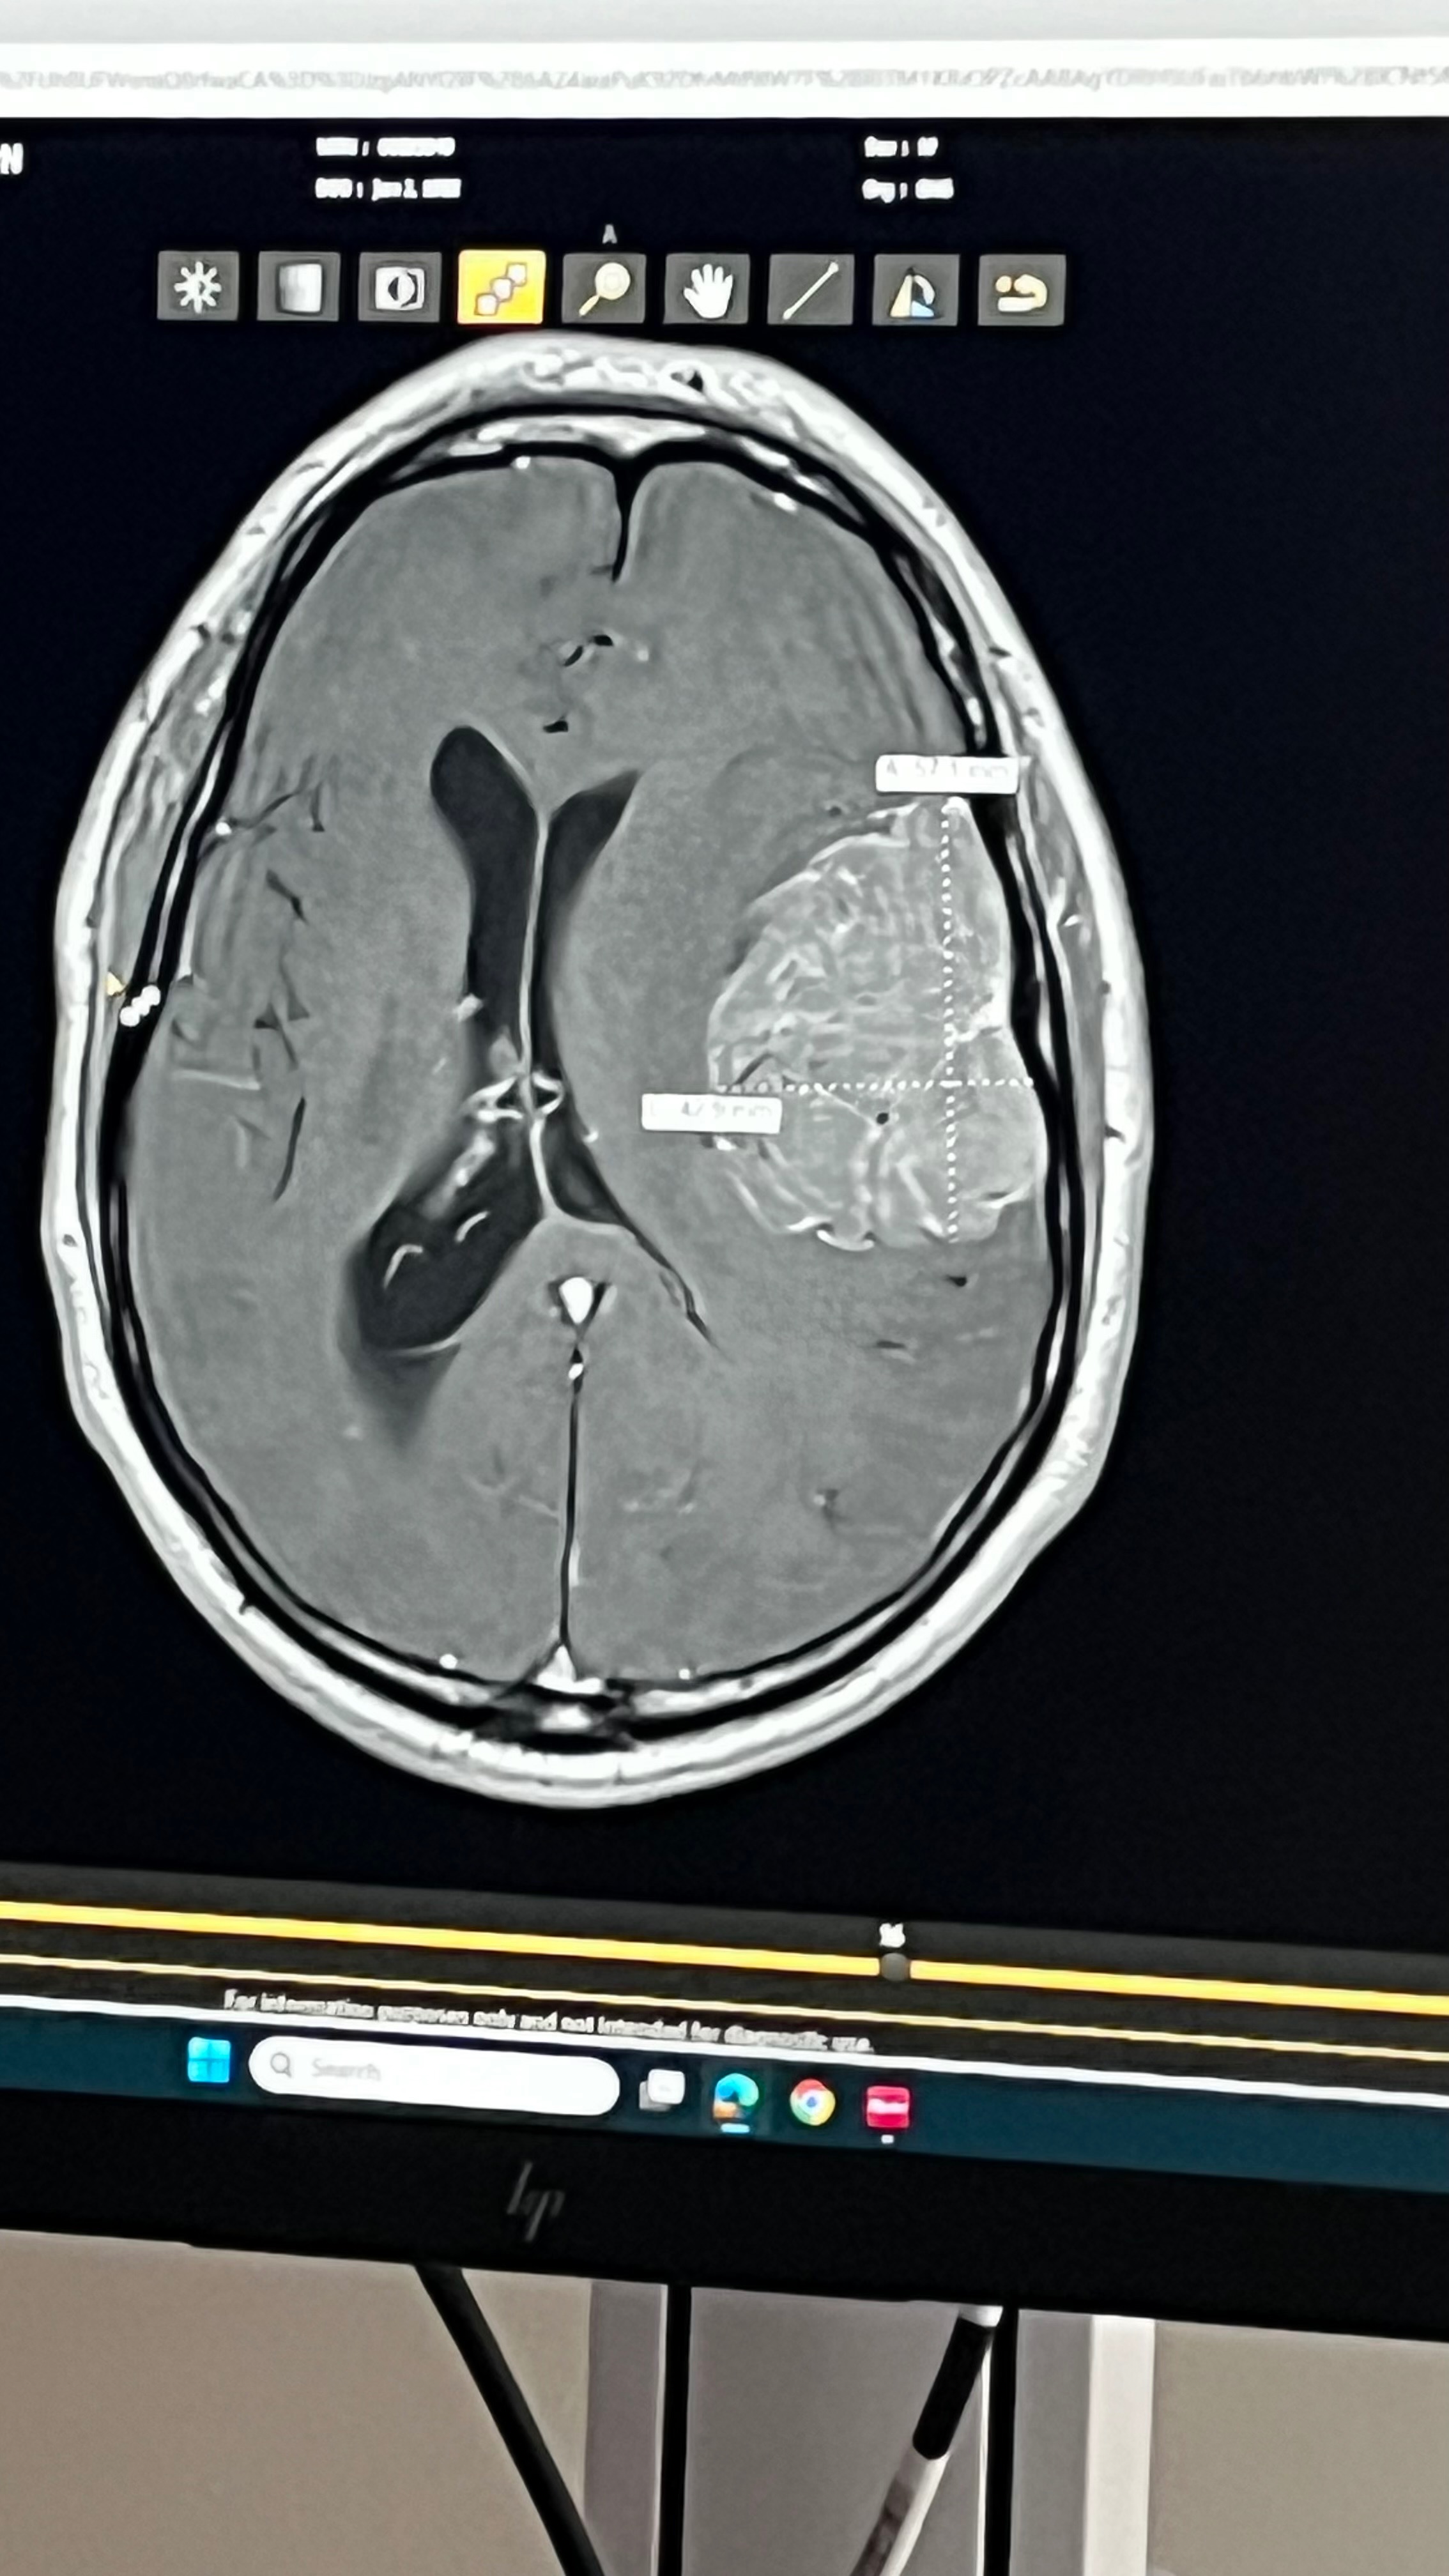

My name is Courtney. I’m starting this GoFundMe for Jason and Jen Case. As many of you know, Beav (Jay) was diagnosed with a 7cm mass on his brain about a month ago. Since then, it’s been just Jenny working, and that was when she could. The first two weeks, no one knew what was going on. I’m sure we couldn’t imagine what they’ve been through during those two weeks, unless you have personally been through it yourself.

Thankfully, they had a very successful surgery that occurred on 10/9/25. The mass has been removed and biopsied. They got the best news today! The tumor was benign!!!